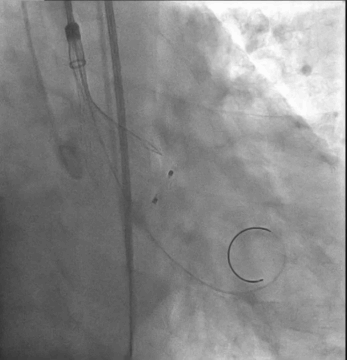

主动脉根部造影提示瓦氏窦整体形态偏小,决定给予冠脉保护

导丝左冠保护

18mm球囊预扩,无明显腰征,少许瓣周漏,未见冠脉阻挡,决定选择TaurusOne®AV23瓣膜。

瓣膜释放后形态位置良好,造影无返流